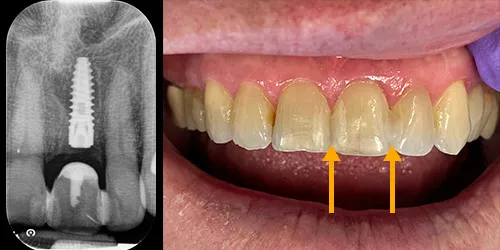

Egen tand, som blev limet mod nabotænderne under helingsprocessen

Røntgenbilledet viser det implantat, der blev placeret umiddelbart efter fjernelse af tanden og “limning“ på nabotænderne.

Billedet viser patientens egen tand, som blev limet mod nabotænderne under helingsprocessen.

Tandkød uden tand, før der blev taget aftryk til krone

Billederne viser situationen, inden tandkødet blev genåbnet – det vil sige lige inden, der blev taget aftryk til kronen.

Efterfølgende blev en såkaldt gingiva-former monteret, som hjalp med at forme tandkødet, mens det helede efter placeringen af implantatet. Den holdt tandkødet åbent, indtil kronen var klar til at blive fastsat cirka 2 uger senere.